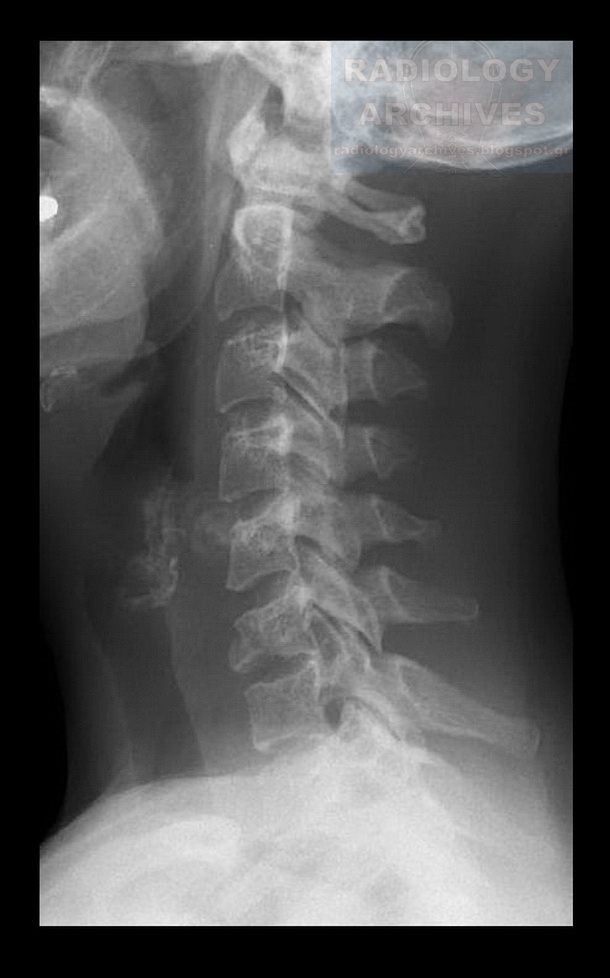

Fracture right pars interarticularis C6 radRounds Radiology Network

From www.radiologyarchives.com

Radiology Archives Φεβρουαρίου 2013 Compression Fracture C6 a compression fracture is a type of broken bone that can cause your vertebrae to collapse, making them shorter. When broken, this bone collapses. vertebral compression fractures (vcfs) of the spinal column occur secondary to an axial/compressive (and to a lesser extent, flexion). This often happens to the front of the. Functions of c6, c7, and c8. . Compression Fracture C6.